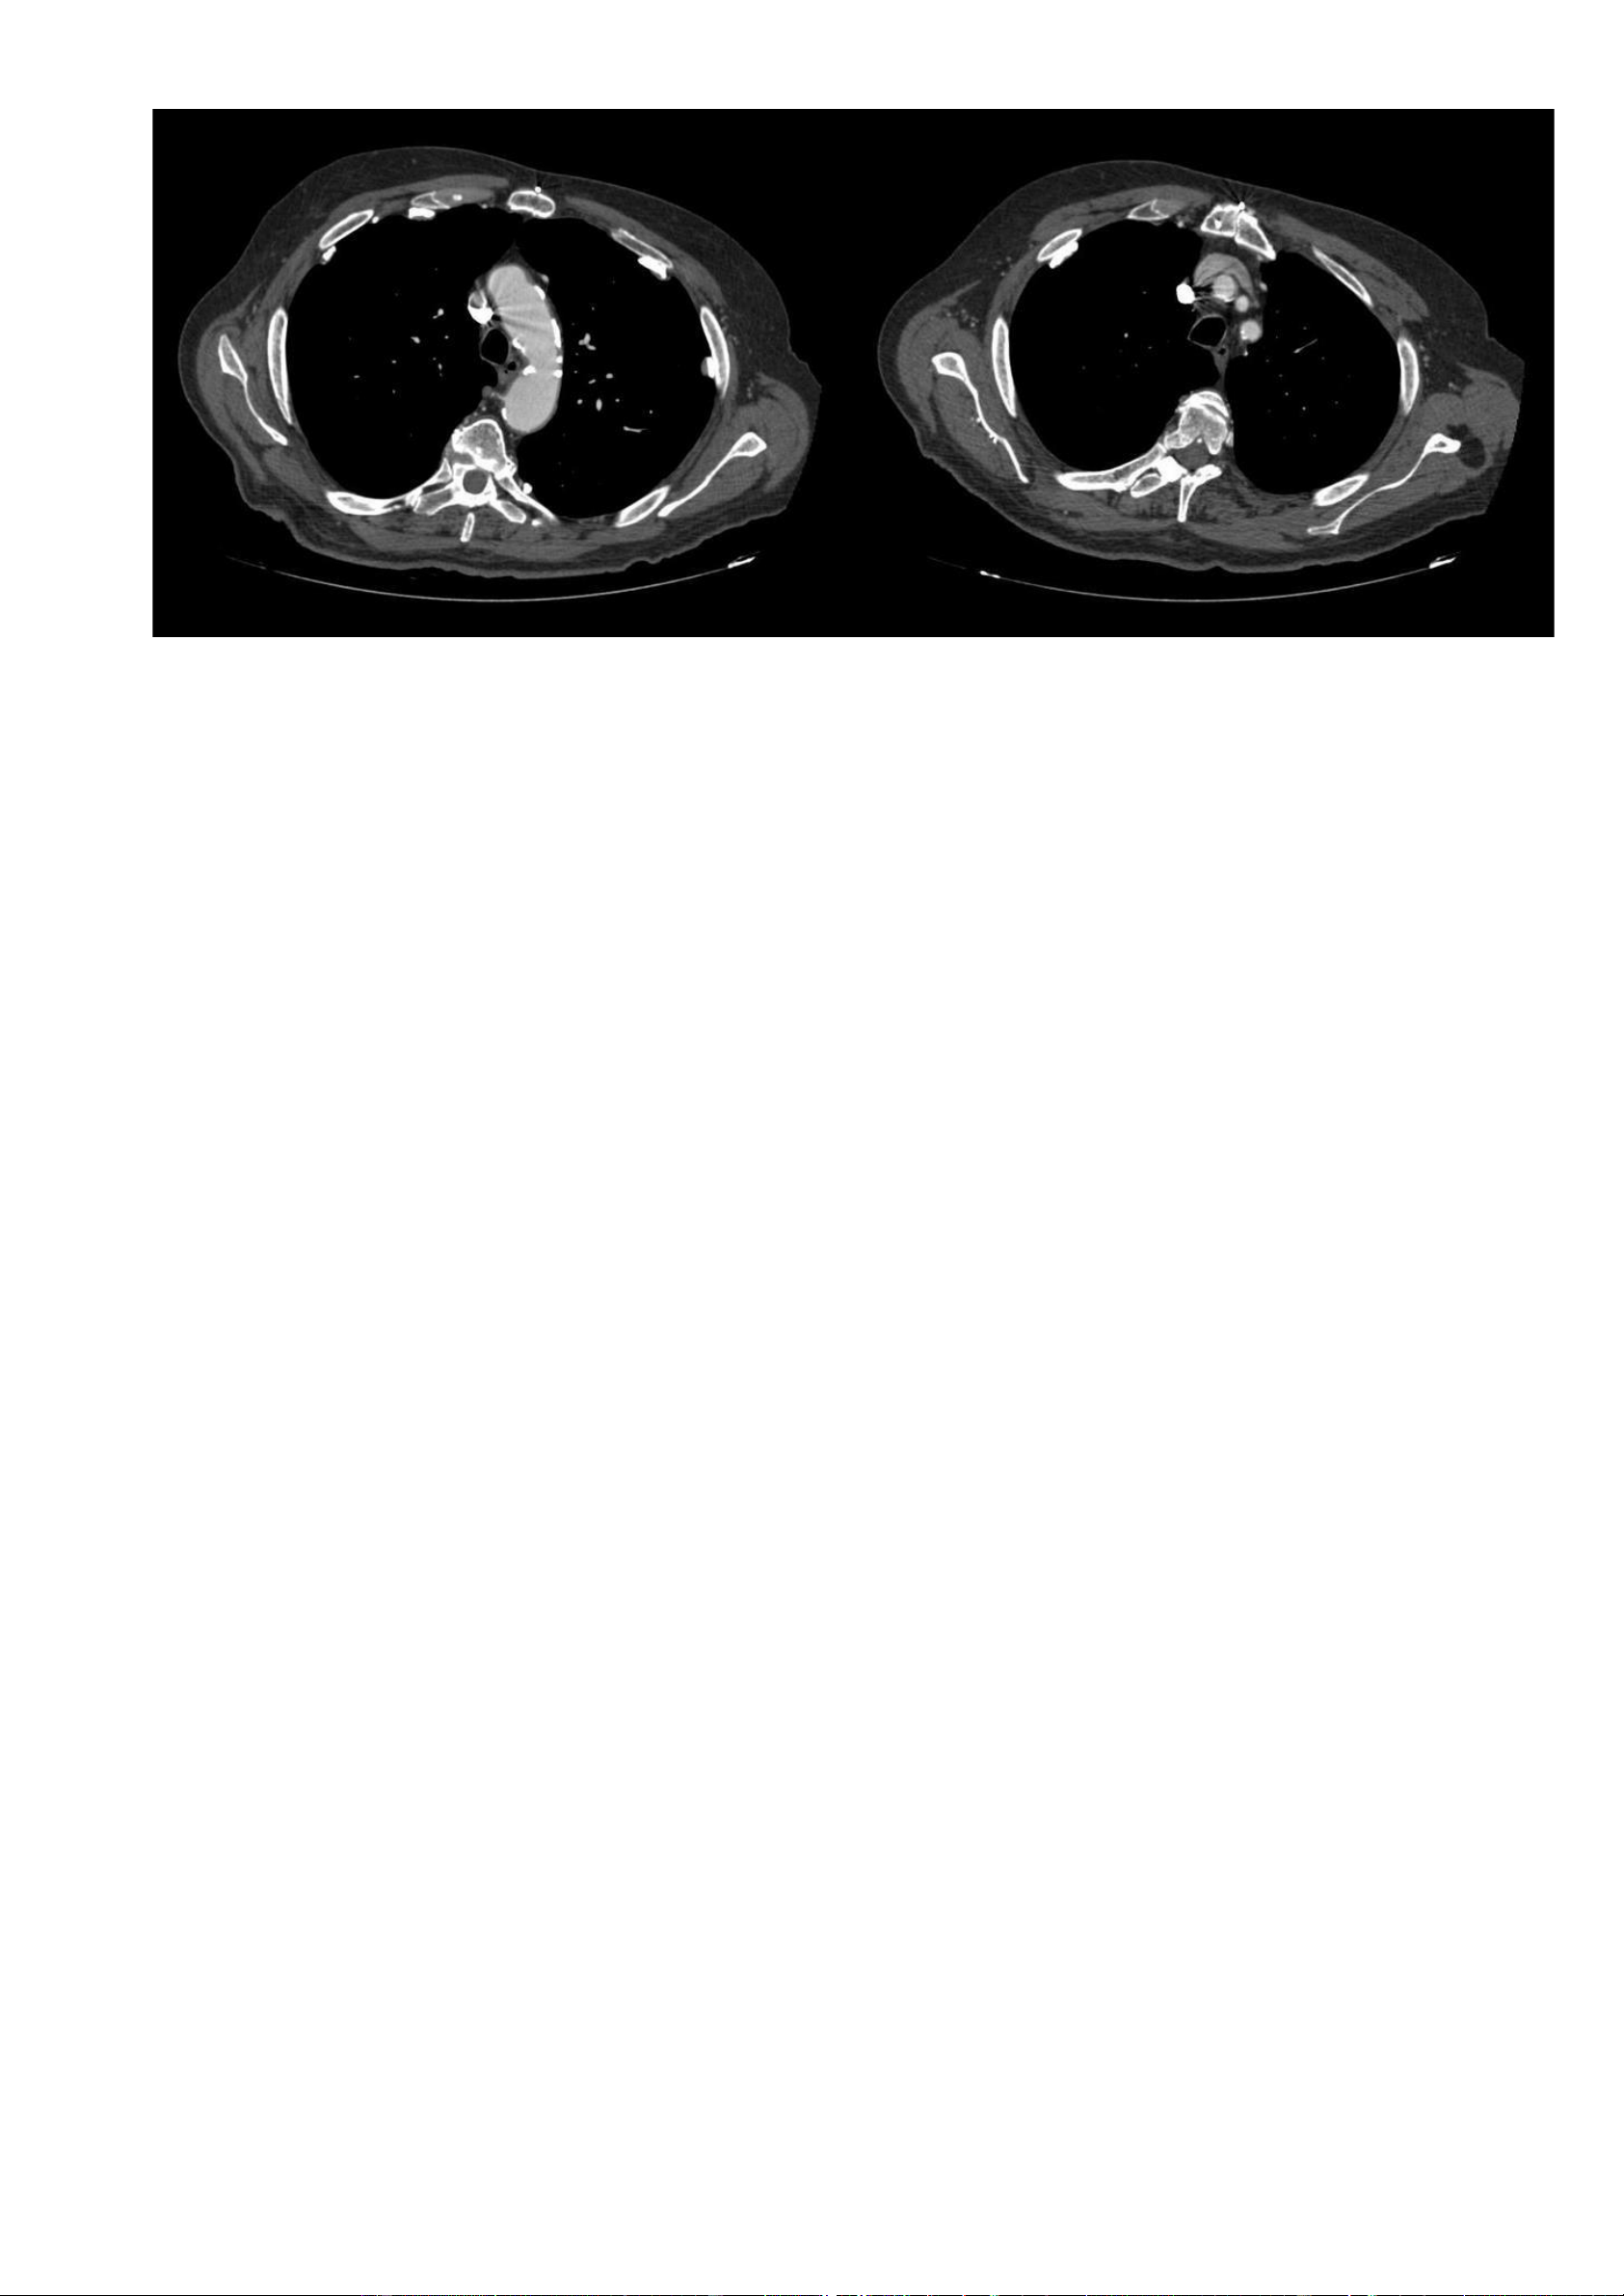

Hình ảnh CT (cửa sổ xương): lOMoAR cPSD| 22014077 Phan Tùng Bách

Các hình ảnh CT được lựa chọn cho thấy sự hiện diện của các màng màng phổi vôi hoá, đặc biệt là ở phần

trước-ngoài của màng phổi thành. Một vài mảng màng phổi không vôi hoá ở phần sau. Màng phổi trung thất và

các góc sườn hoành bình thường. 7.2. Trường hợp 2: -